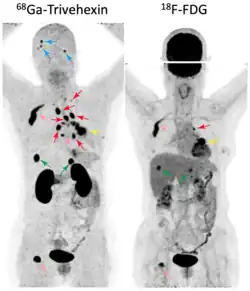

A prospective clinical study (NCT05835570)[38] involving 58 participants with non-small cell lung cancer (NSCLC) compared the diagnostic performance of 68Ga-Trivehexin PET/CT with 18F-FDG PET/CT.[37] Both radiotracers showed similar diagnostic accuracy (100%, 58/58) for the detection of primary tumors. The sensitivity for detection of lymph node metastases was comparable for 68Ga-Trivehexin (80%) and 18F-FDG (72%), but 68Ga-Trivehexin showed a higher specificity (93.8%) and accuracy (91.2%) than 18F-FDG (62.5% and 64.2%, respectively). Sensitivity for detecting brain metastasis was 92.3% for 68Ga-Trivehexin and 38.5% for 18F-FDG, mainly because of the high glucose consumption of normal brain tissue, which usually results in a high physiological uptake of 18F-FDG in the brain, generating a strong background signal which frequently obscures brain metastases in PET images (see image).

In a cohort of 20 suspected (19 confirmed) head-and-neck squamous cell carcinoma (HNSCC) cases, 68Ga-Trivehexin PET had a higher sensitivity (92.5%), positive predictive value (PPV, 100%), and accuracy (93%) than the standard 18F-FDG PET, for which sensitivity, PPV, and accuracy were 90%, 93.1%, and 84.3%, respectively.[32] 68Ga-Trivehexin was furthermore applied in a case of tonsillar carcinoma metastasized to the brain (see image).[31]